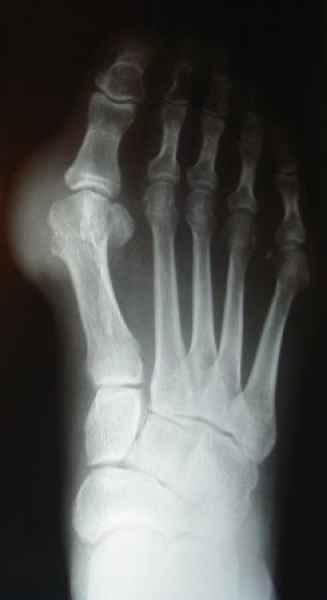

El pie es el órgano distintivo y característico de la especie humana, la única criatura que marcha erguida. El pie es una muy compleja estructura de arquitectura perfecta, adaptado a su función de apoyo, traslación, salto, con una riquísima sensibilidad que le permite detectar las más leves imperfecciones del suelo para estabilizar la marcha.

Tanto la estructura del pie como su funcionalismo que es la marcha, pueden ser asiento y manifestación respectivamente de alteraciones locales ó sistémicas, por lo que su cuidadoso examen resulta de extrema utilidad diagnóstica.